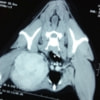

症例:腋窩部の軟部組織肉腫 ウェルシュ・コーギー 11歳 去勢オス

CT写真

右前肢の破行および疼痛を主訴に来院。消炎剤による内科療法にて疼痛の改善はあるものの、破行の継続および神経反射の低下が認められたため、MRIおよびCT検査を実施。

CT所見:右腋窩部に腫瘤の形成を確認